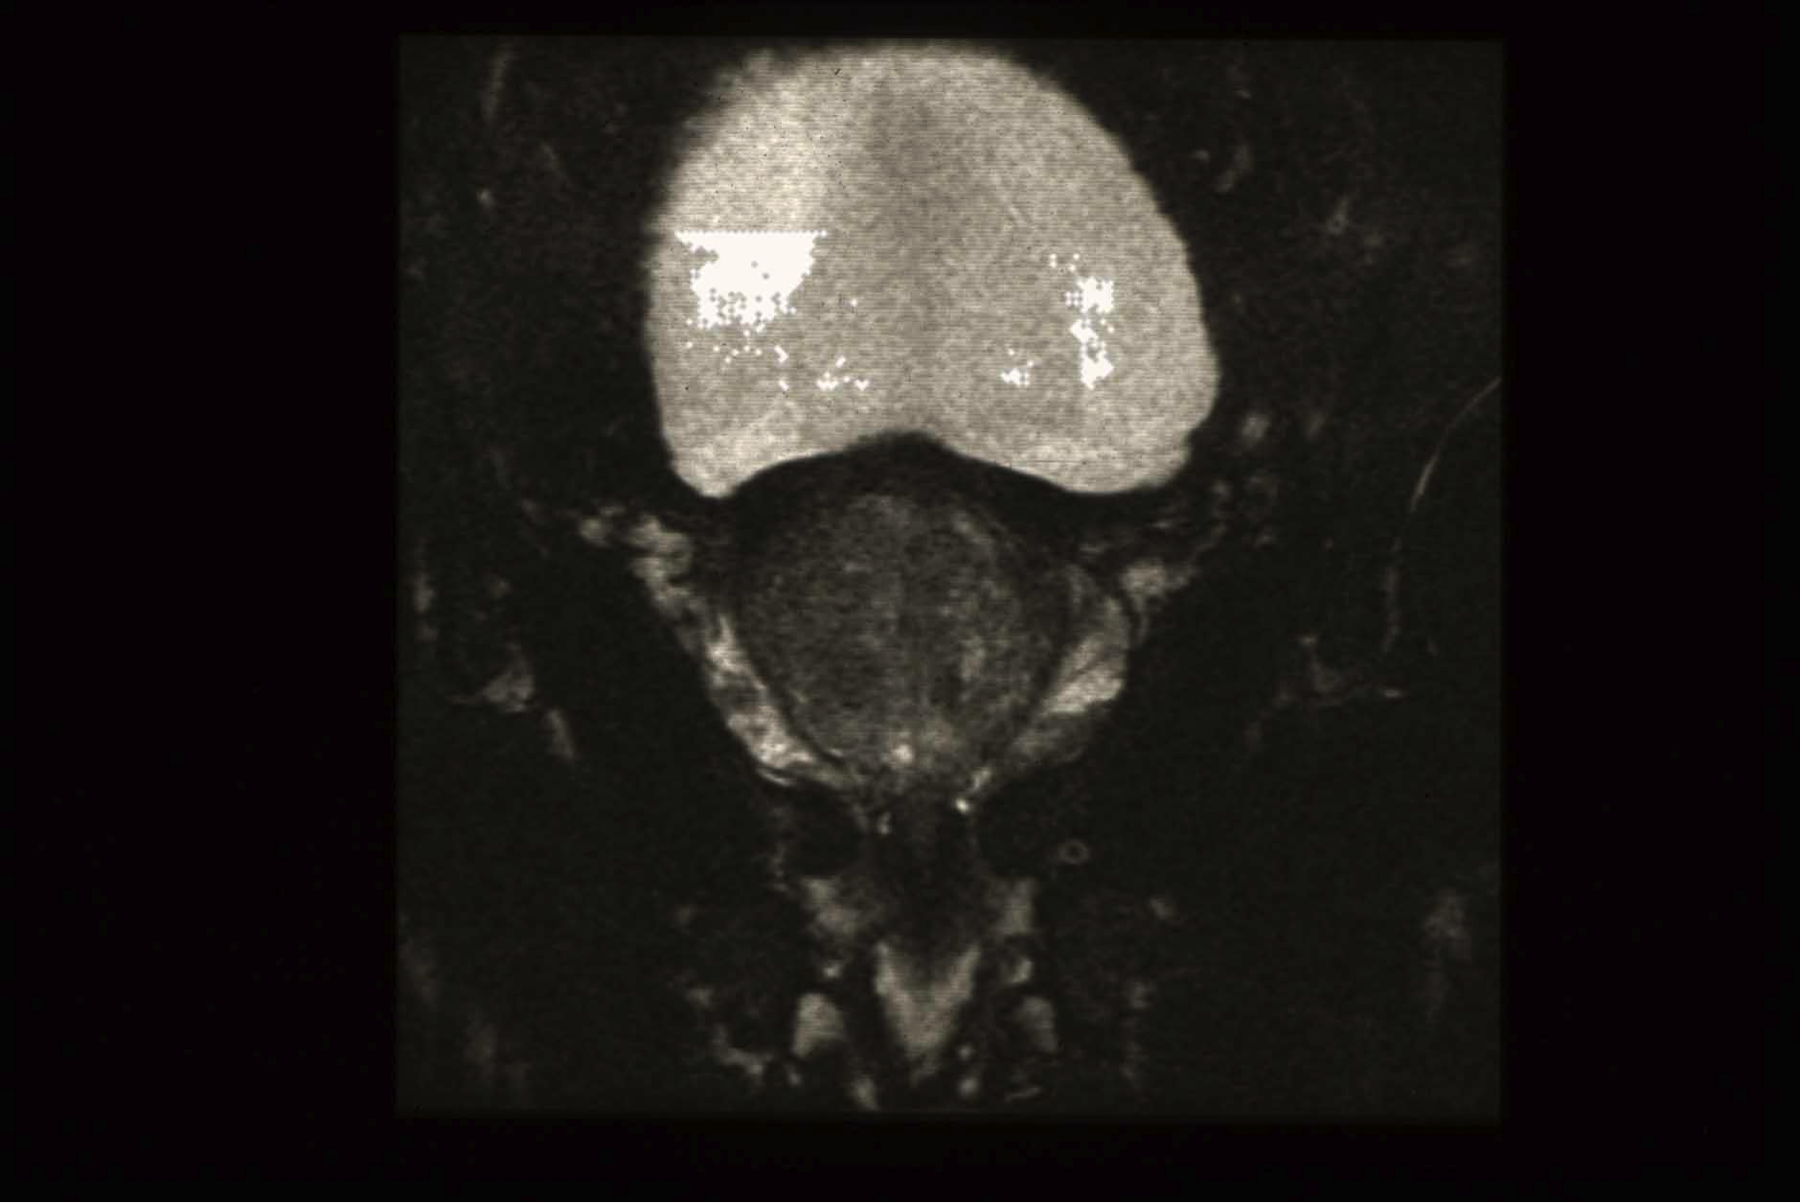

suffering-for-science-mri-bladder